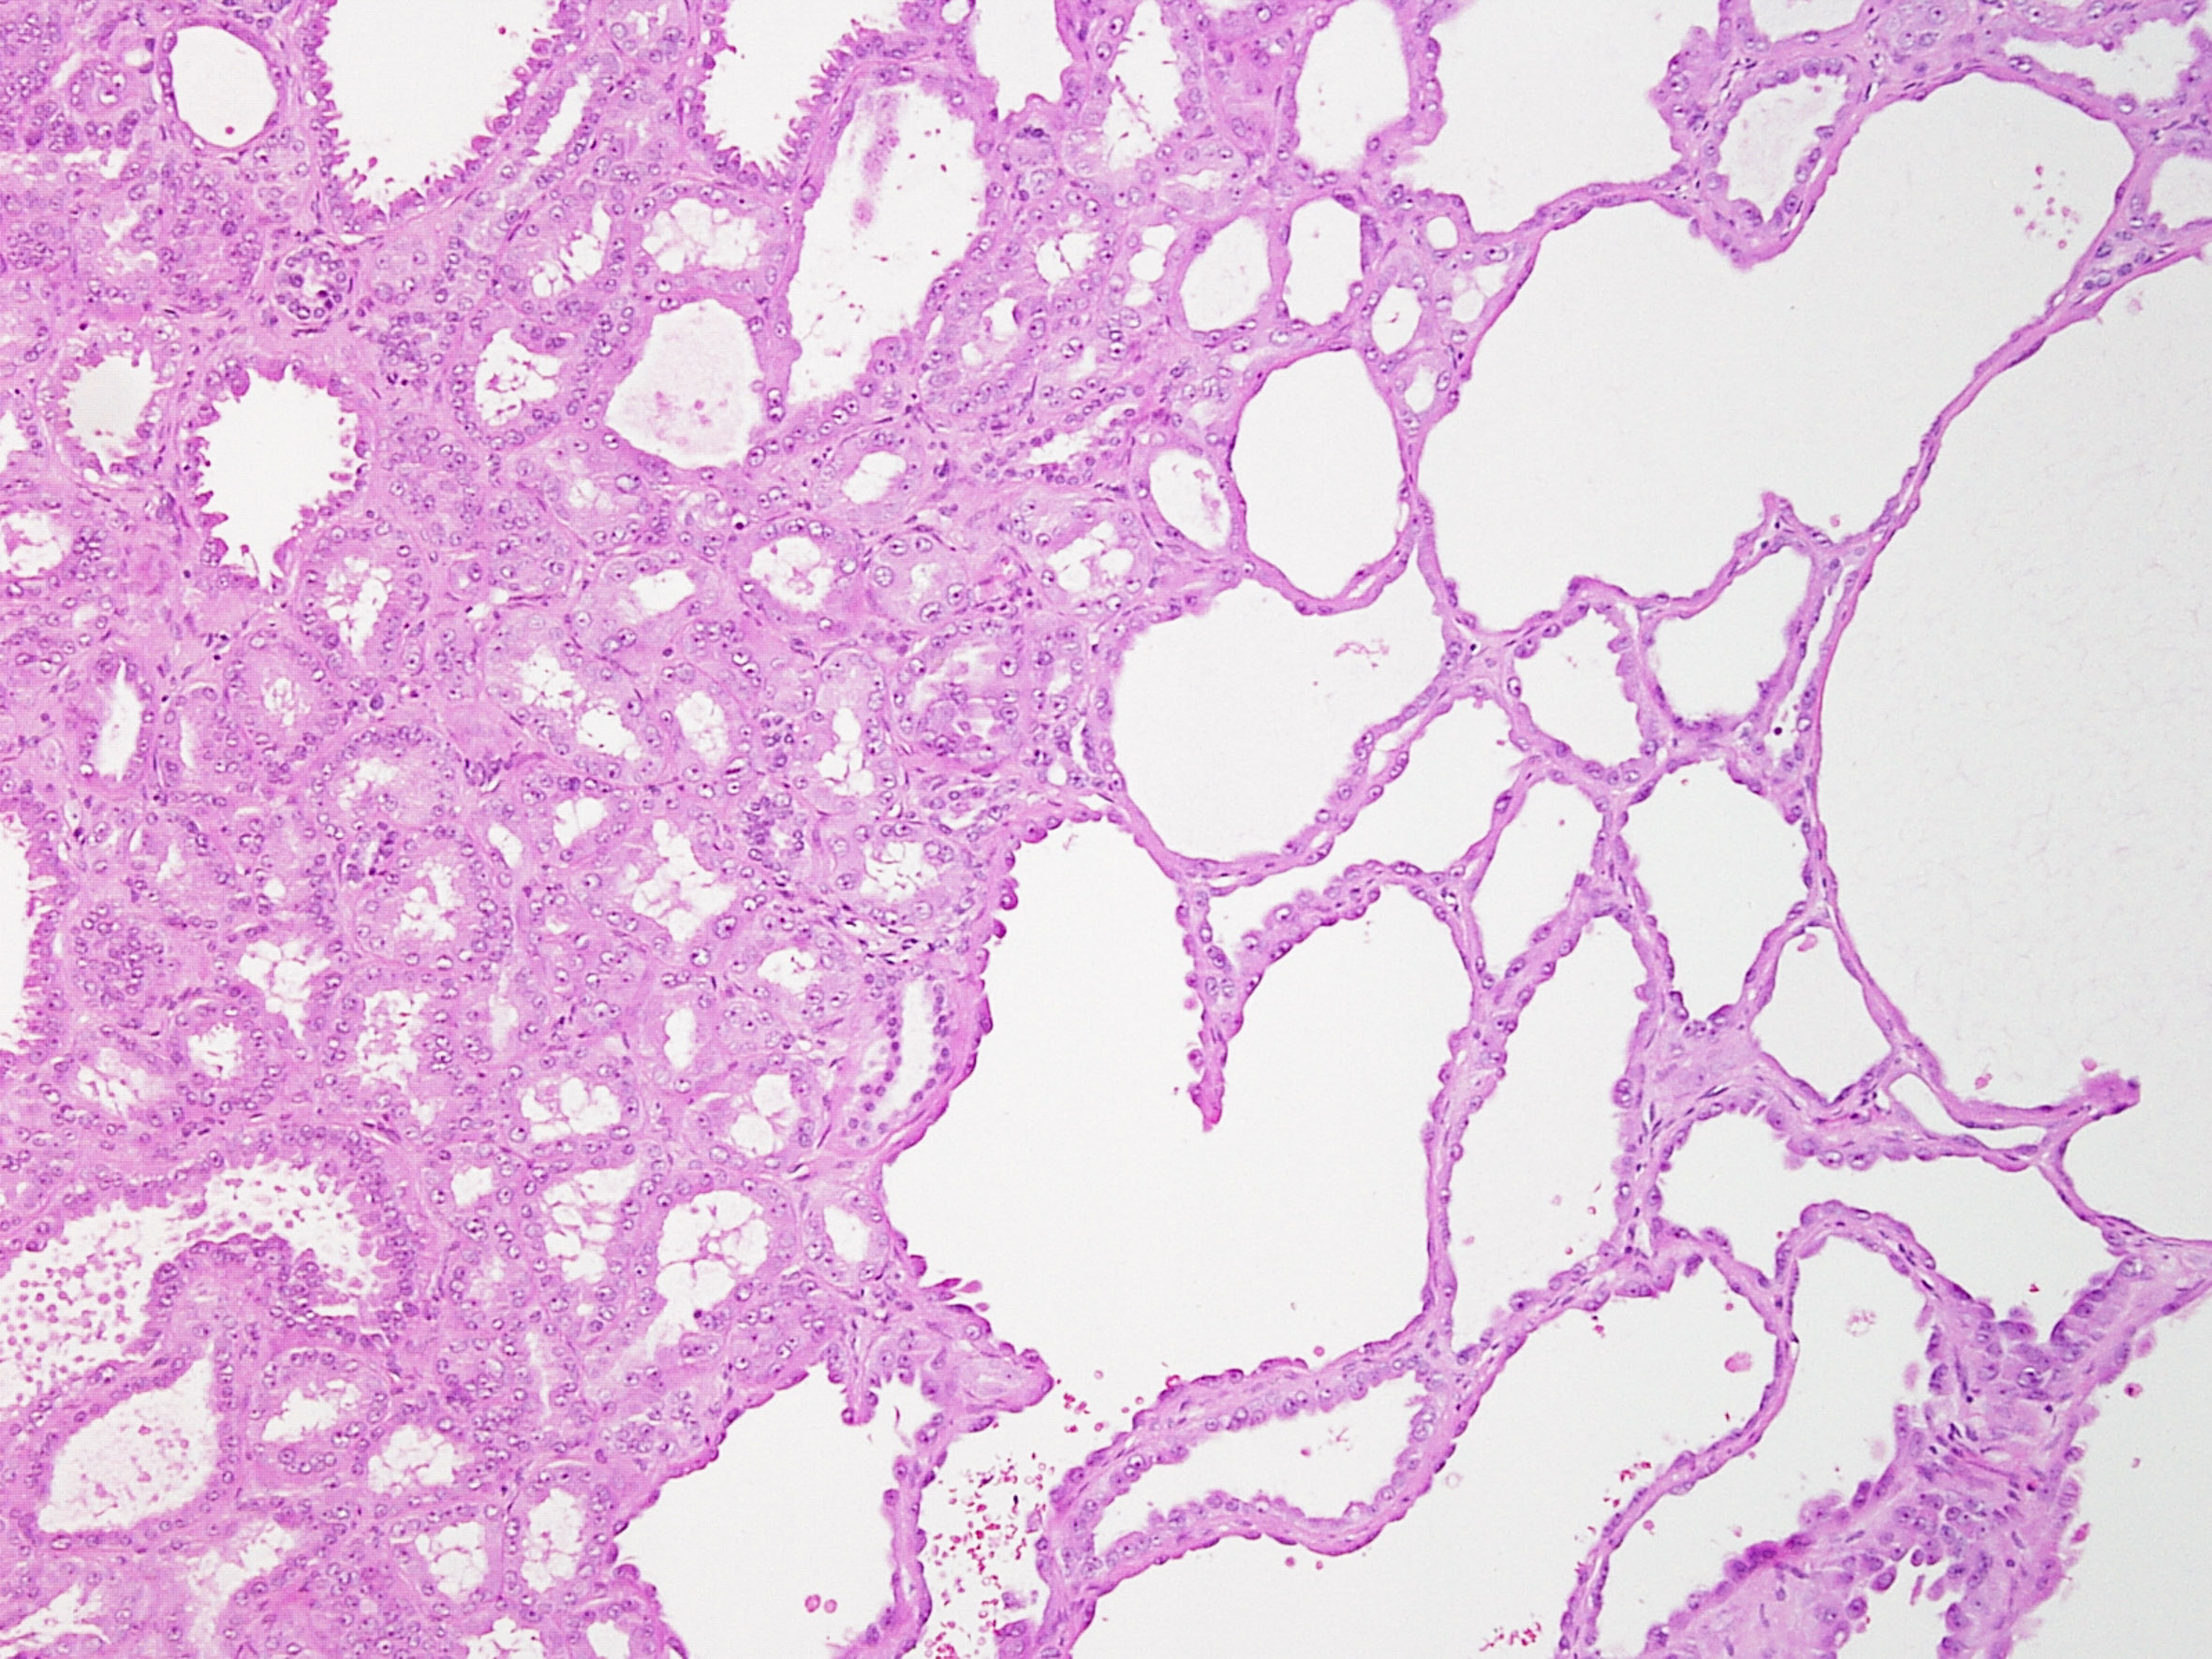

Consensus grade: Tubulocystic RCC

Tubulocystic renal cell carcinoma